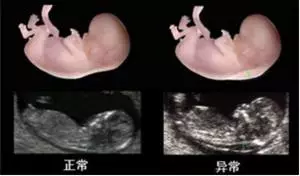

第一:孕10~14周检查,主要测量胎儿颈部透明层厚度(NT),并排除无脑儿等早期即可出现的大畸形。